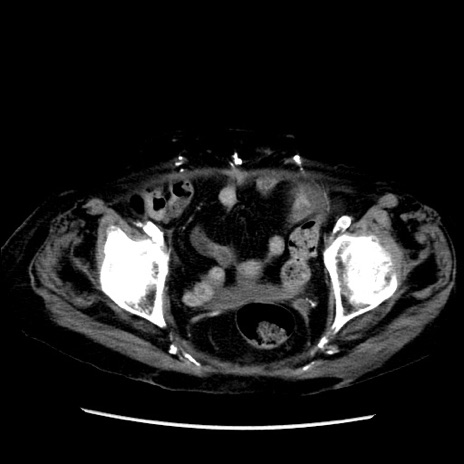

症例14(横断像)

【症例】 90歳代女性

【主訴】 腹痛・嘔吐

【現病歴】今朝から左側腹部痛を認めた。 経過観察していたが、嘔吐を認めたため来院。

【既往歴】 子宮癌術後

【身体所見】 意識清明、BP 127/54mmHg、P 98bpm Sp02 95%(RA)、BT 35.8°C、腹部平坦・軟腸ぜん動音聴取良好、右下腹部圧痛(+) 反跳痛なし

【データ】WBC 9800、CRP 0.46